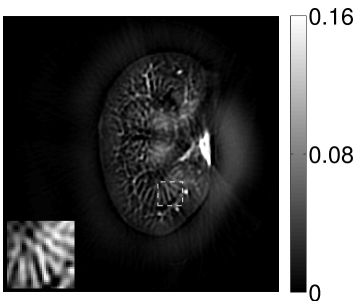

VI-E Results: kidney phantom

The images and EIRs reconstructed by use of the VP algorithm that was based on the 2D imaging model that neglected the SIR are shown in Figures 15 and 16. The latter figure contains results corresponding to different values for the regularization parameter . From Fig. 15, it can be observed that use of the conventional iterative method that utilized the measured EIR resulted in distortions and loss of details in the reconstructed images. Use of the VP algorithm improved the contrast and the details in the reconstructed images (Fig. 15(c) and 16(a)). Furthermore, the images reconstructed by use of the VP algorithm had a more uniform background.

In Figure 17, the results corresponding to use of the 3D imaging model that incorporated SIR effects are shown. The EIR estimated by the VP algorithm is also shown. In Figure 18, images and EIRs reconstructed by use of the VP algorithm with different regularization parameters values are shown.

Similar to the case described above where the transducer SIR was neglected, these results reveal that use of the VP algorithm can produce images with a cleaner background and enhanced spatial resolution than yielded by use of a conventional iterative algorithm that employed the measured EIR. For example, detailed information regarding the vessels near the organ’s periphery was better preserved by the VP algorithm than by the conventional iterative algorithm. These images corroborate our assertion that the VP algorithm can significantly reduce the artifacts and distortions in the reconstructed image. It is also worth pointing out that, unlike the numerical phantom studies, the artifacts and distortions in the images may be caused not only by the inaccurate EIR but also by other factors, such as neglecting acoustic heterogeneities and the variation of the EIRs among the elements of the transducer array. In such cases, the EIR estimated by the VP algorithm represents an effective system impulse response that minimizes the inconsistency between the measured data and the imaging model.